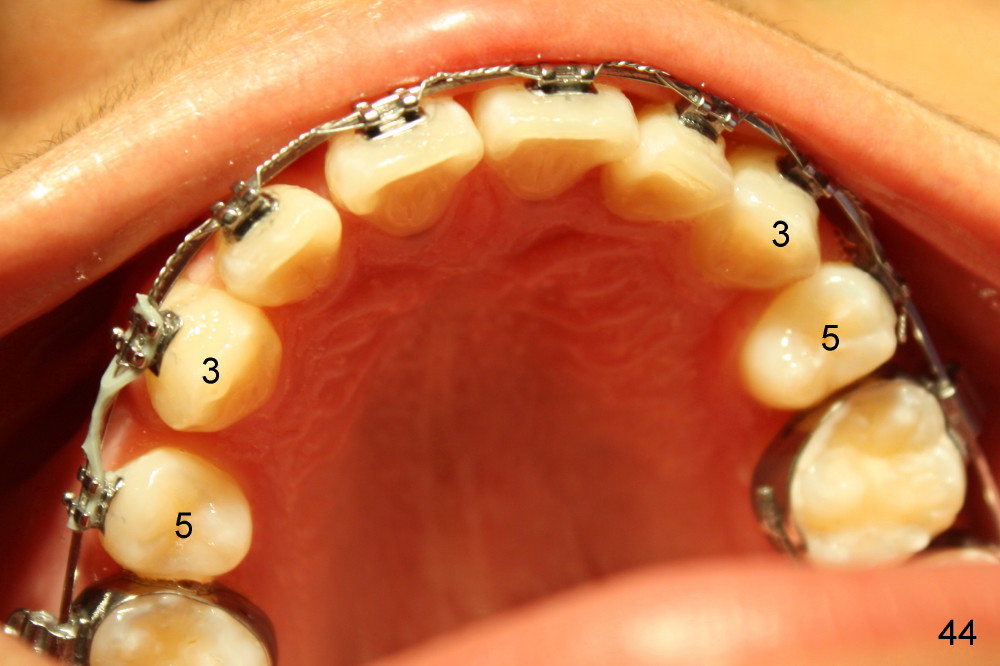

Four and a half months post bracketing (Fig.21-25), what do you find and what should be done next?

Prior to bracketing, the mesiodistal space for #18 is planned to be obtained by moving #20 and then #19 mesially (Fig.31-35, 16x16 ss). The six anterior lower teeth are tied together in a figure 8 fashion. Power chains are placed between the lower canine and the 2nd bicuspids. The upper diastemata are to be closed by power chains between the 1st molars.